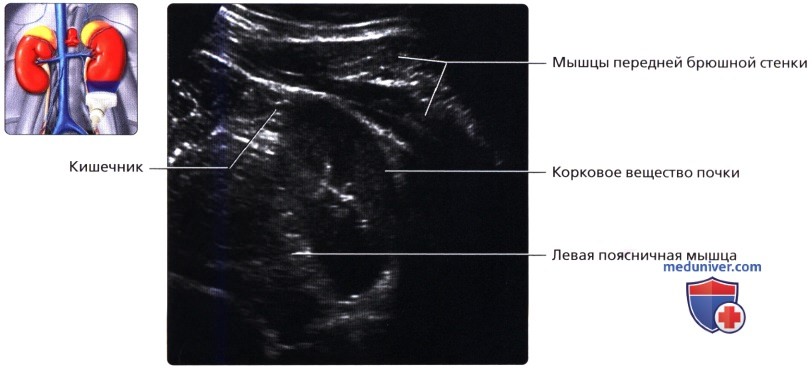

Несмотря на то что почки располагаются в забрюшинном пространстве, от кишечника их отделяет лишь пристеночный листок брюшины. Такая близость органов по отношению друг к другу может затруднять диагностику в случае значительного скопления газов в ЖКТ.

а) Анатомия почек:

2. Топографическая анатомия почки:

• Лежат в забрюшинном пространстве, окружены почечной фасцией (фасция Героты)

• У взрослого каждая почка около 9-14 см в длину и 5 см в ширину

• Обе почки лежат «на» квадратных мышцах поясницы, латеральнее поясничных мышц

б) Лучевая анатомия почки:

1. Обзор:

• Забрюшинные структуры бобовидной формы с четким контуром, смещающиеся при дыхании

в) Особенности визуализации почек:

1. Рекомендации по визуализации:

• Правая почка:

о Печень используется в качестве акустического окна

о Датчик устанавливается в подреберье или в межреберный промежуток

о Выполняйте исследование при различной глубине вдохе

о Попросите пациента немного повернуться влево, приподняв правый бок и выполняйте сканирование с боковой/заднебоковой поверхности

• Левая почка:

о Ее труднее визуализировать из-за газа в тонкой кишке и в селезеночном изгибе ободочной кишки

о Обычно левую почку проще визуализировать, используя заднебоковой эхографический доступ и попросив пациента немного повернуться вправо приподняв левый бок

о В сложных случаях полностью переверните пациента в положение лежа на правом боку, подложите подушку под его правый бок и попросите его поднять левую руку над головой:

— Для исследования верхнего полюса левой почки можно использовать селезенку как акустическое окно

о Задний эхографический доступ:

— Удобен при инвазивных процедурах (биопсия почки, нефростомия)

— Качество изображения может снижаться из-за теней от околопозвоночных мышц и ребер